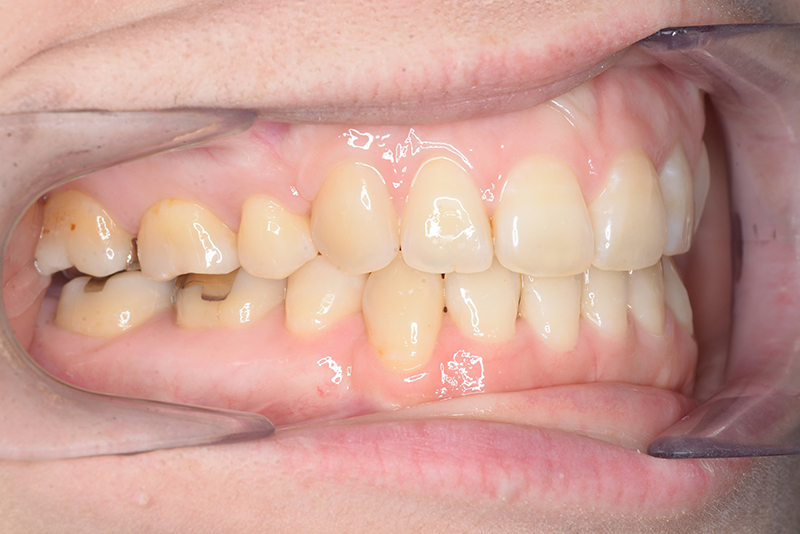

| 主訴 | 前歯で物が噛めない | 診断名 | アングルⅠ級開咬症例 | ||||

|---|---|---|---|---|---|---|---|

| 初診時年齢 | 37歳8ヵ月 | 性別 | 女 | 動的治療期間 | 23ヵ月 | ||

| 批評・予后 | 治療後において下顎角の開大も認められず歯軸の整直、咬合の緊密化が得られた。また上下顎前歯の後退と共に口元の突出感と口唇閉鎖不全の改善が認められた。 |